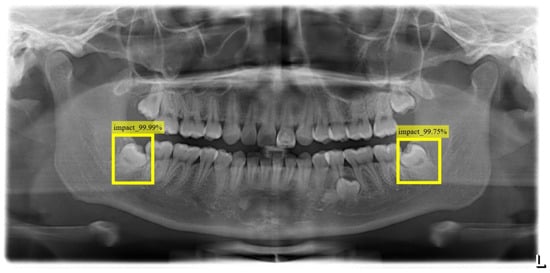

This study uses YOLO_V4 and vertical grayscale projection algorithms to locate the positions of impacted teeth and the inferior alveolar nerve. YOLO_V4 is an object recognition model, often used for detection or license plate recognition. In this research, YOLO_V4 was applied to identify impacted teeth and the inferior alveolar nerve in DPR images. This study annotated 500 DPR images for YOLO_v4 training, with the validation results depicted in Figure 9, showcasing an impressive accuracy of up to 88%. The YOLO model records both the position and class of bounding boxes, enabling the extraction of impacted teeth based on the recorded positions. The proposed impacted tooth segmentation algorithm, based on vertical grayscale projection, achieves an accuracy rate of 93%. Comparative analysis utilizing 100 untrained images against prior research outcomes, as presented in Table 1, reveals that the leveraging of the proposed impacted tooth segmentation algorithm in this study demonstrates an enhancement in accuracy by 3–5% compared to previous research and YOLO_v4.

Figure 9. The results of YOLO_V4 detection for impacted teeth and the position of the IAN.